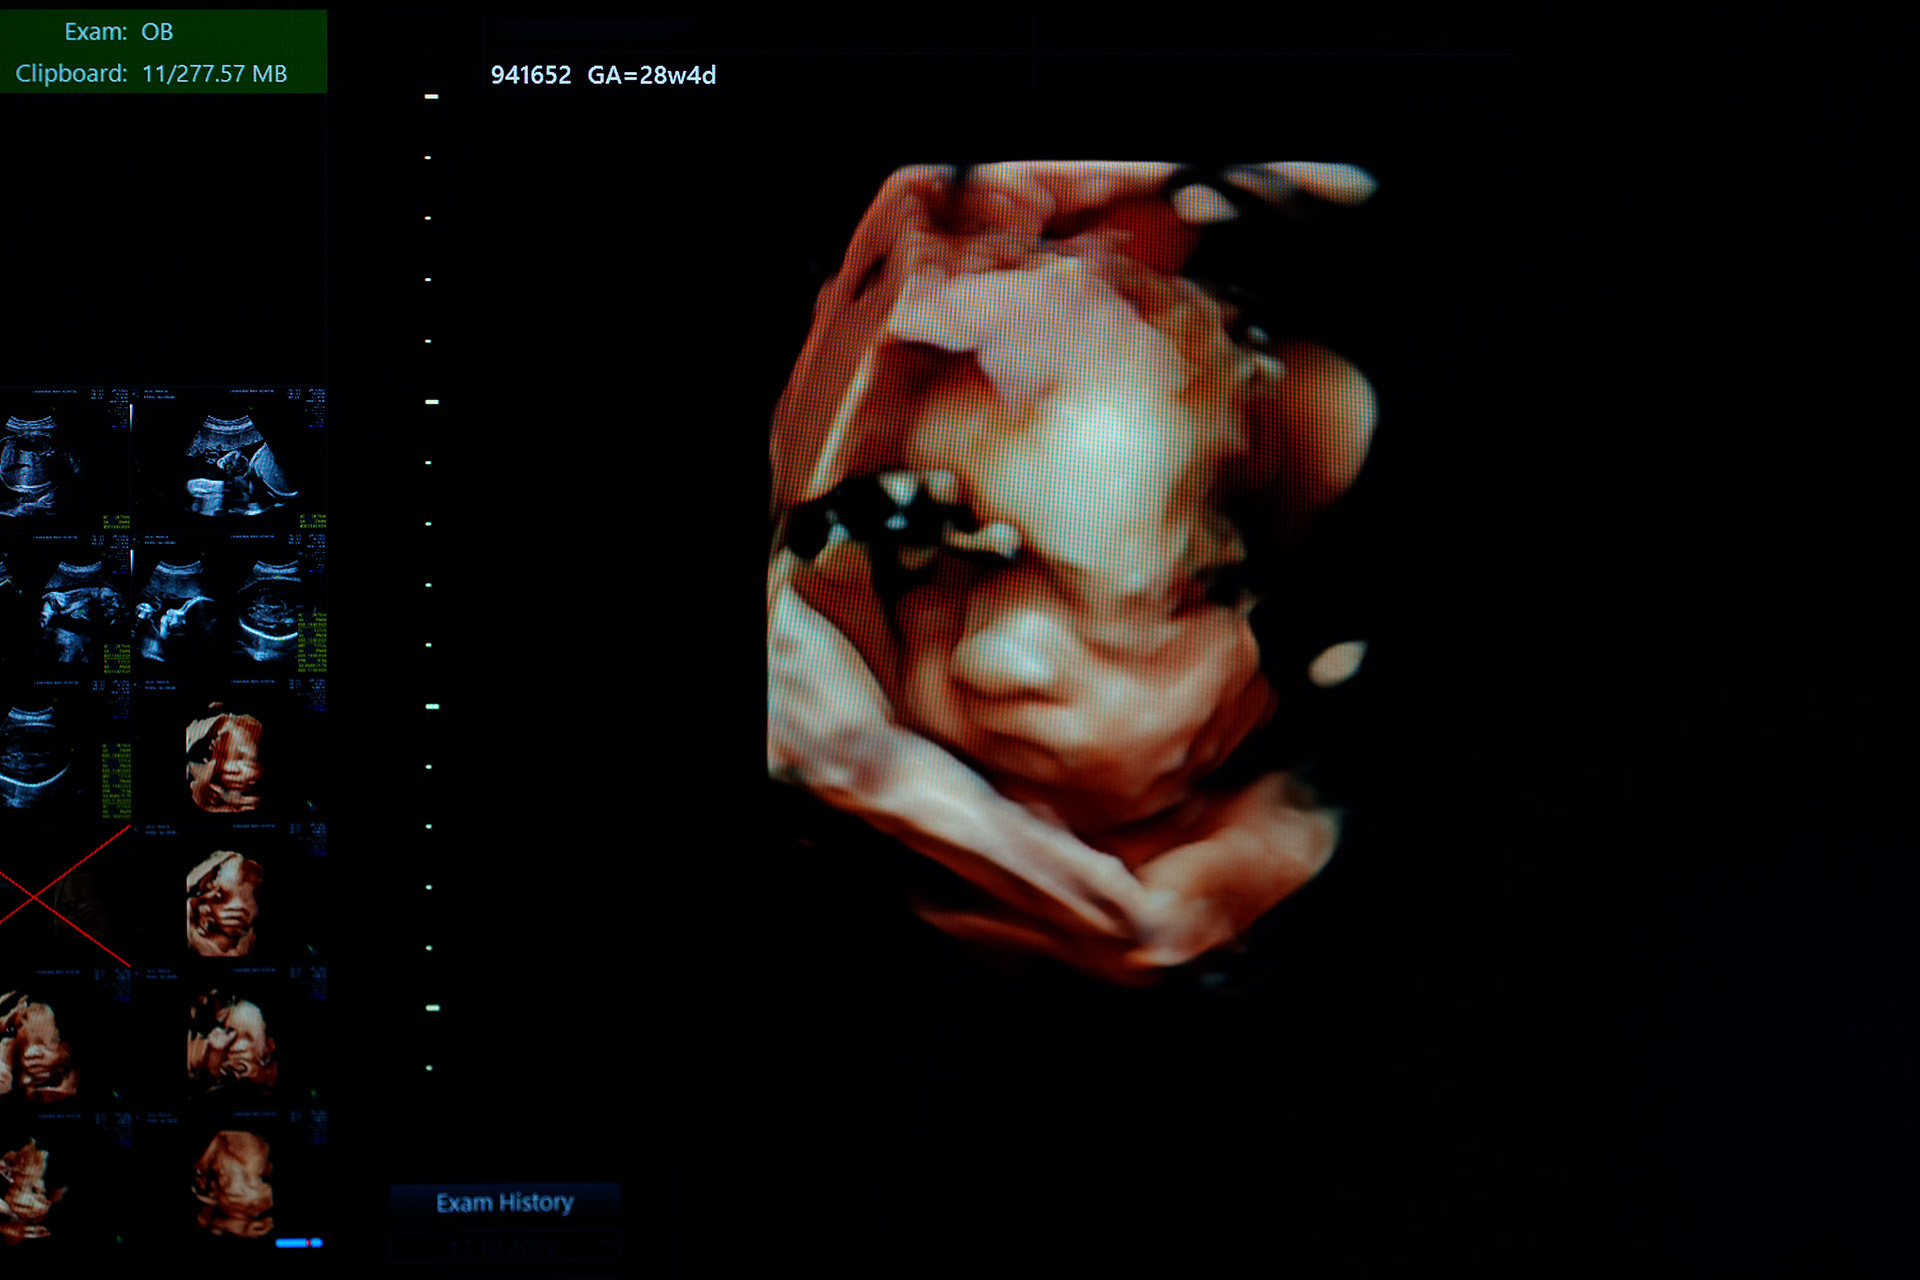

Мы можем «поймать» его на УЗИ. Во время беременности проводятся три обязательных ультразвуковых исследования: первое мы делаем с 11 по 14 неделю, второе — между 18 и 21 неделями, третье — на сроке 34–36 недель. Уже на первом из этих скринингов при обследовании монохориальной двойни можно заподозрить специфические осложнения: фето-фетальный трансфузионный синдром или синдром селективной задержки роста, когда один из детей растёт соответственно сроку, а другой — нет. Из-за вероятности развития этих осложнений монохориальные двойни должны проходить ультразвуковые обследования значительно чаще: как минимум 1 раз в две недели после 16-й недели. Так что заподозрить и своевременно подтвердить такие отклонения мы можем достаточно рано.

Это касается не только хирургии. Ключевым моментом становится пренатальная ультразвуковая диагностика: даже если мы не делаем никакую операцию, но вовремя замечаем тяжёлый порок развития, который потребует вмешательства после рождения, пациентка с большей вероятностью окажется в учреждении, где ребёнку после рождения окажут всю необходимую помощь. Отсутствие информации о пороке развития может привести к тому, что пациентка будет рожать в обычном родильном доме, где нет отделения неонатальной хирургии. Так что самое главное — вовремя поставить правильный диагноз. Знать о проблеме, с которой придётся столкнуться семье ещё до рождения ребёнка, и иметь возможность принять правильное решение — это очень важно.